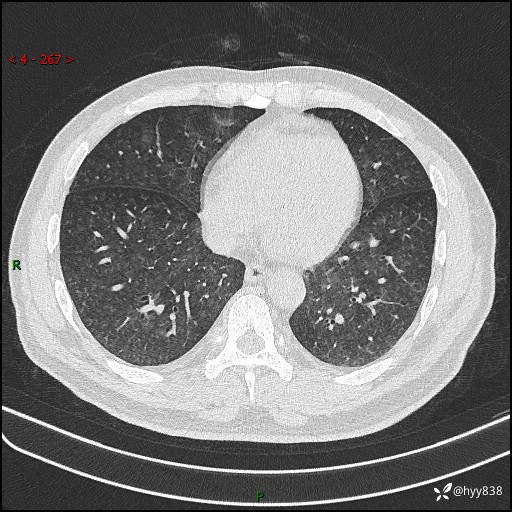

昨天肺结节门诊,“对门”呼吸科申请会诊病例,弥漫性肺部病变---结果公布~

患者年龄:51岁

主诉:发热、咳嗽、咳痰1周

简要病史:患者1周前无明显诱因出现咽喉部疼痛,随后出现咳嗽咳痰,起初干咳为主,后出现咳少许绿色痰,当时有发热,体温为39℃,无畏寒寒战,无胸闷胸痛,无活动后气短,无咯血,无鼻塞流涕,无全身酸痛,患者于诊所输液治疗后体温正常,但仍有咳嗽。患者3天前当地县人民医院就诊,患者仍有咳嗽,咳嗽较为频繁,咳嗽后出现头痛,伴有少许咳痰,随后出现活动后气短,1天前患者再次出现发热,体温最高为40℃,伴有畏寒寒战,伴有乏力、纳差,伴有胸闷不适,无咯血,无全身皮疹,无血尿、尿频尿急尿痛,无腹泻,诊断为“重症肺炎 感染性休克 肾功能异常 痛风”;予以抗感染(亚胺培南),抗病毒(奥司他韦)等对症治疗。患者复查胸部CT提示双肺病灶较前有所增多,建议上级医院就诊,门诊以“肺部感染”收入我科。 起病以来,患者食欲欠佳,大小便正常,睡眠、精神欠佳,体力下降、体重无明显变化。

辅助检查:CT

临床诊断:肺部感染

胸部HRCT